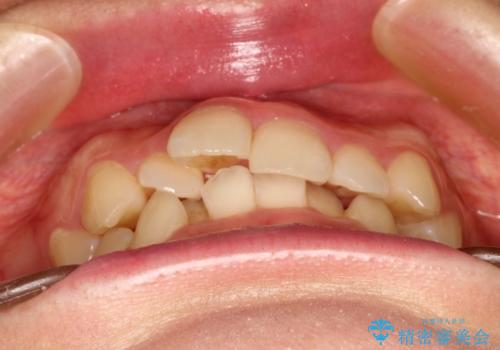

全体的ながたつき ワイヤーによる抜歯矯正で整った歯並びへ

- 上下の全体的ながたつきが気になるとのことで来院されました。

上下左右の前から4番目の歯を抜歯をして、ワイヤー矯正にて並べる計画としました。